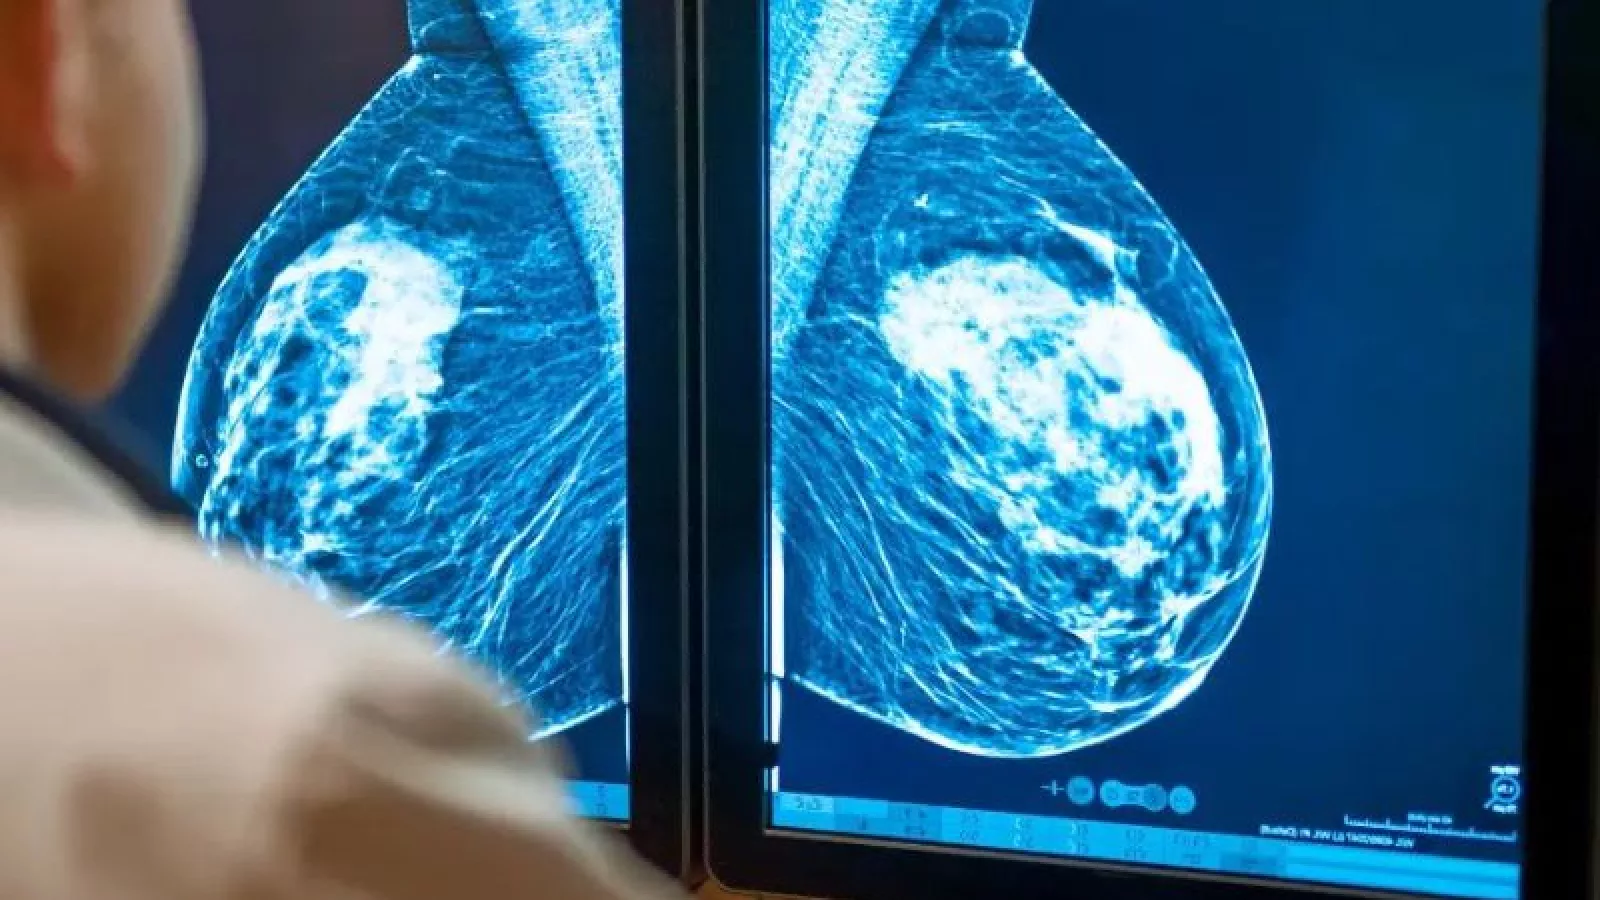

Con el aumento global de la carga sanitaria debido al cáncer2, los sistemas de salud afrontan cada vez más desafíos y buscan soluciones con las que poder avanzar en la detección temprana y el diagnóstico en el momento en que los tratamientos son más efectivos. Para abordar estos desafíos y ofrecer soporte clínico en la detección de este tumor, las dos compañías se centrarán inicialmente en integrar la solución clínica SmartMammo de DeepHealth, una solución SaaS basada en IA y diseñada de cara a los procesos de diagnóstico en cáncer de mama, mejorando la precisión diagnóstica3 y la eficiencia; con el sistema de mamografía Senographe Pristina de GE HealthCare; diseñado para reducir la ansiedad del paciente desde el momento de entrar en la sala para el examen.

Esta colaboración también contempla el desarrollo de un sistema de alertas sobre lesiones potencialmente sospechosas que los centros sanitarios podrán recibir en minutos, lo que hará posible poder llevar a cabo exámenes diagnósticos en el mismo día, mejorar el seguimiento, así como también reducir la ansiedad del paciente en este aspecto, además de la incertidumbre.

“Mientras buscamos hacer realidad una atención mamaria más personalizada, la IA sigue demostrando ser muy prometedora en la detección del cáncer de mama, desde la detección temprana y la predicción del riesgo hasta la reducción de las devoluciones de llamadas y flujos de trabajo más eficientes para los proveedores de imágenes mamarias.